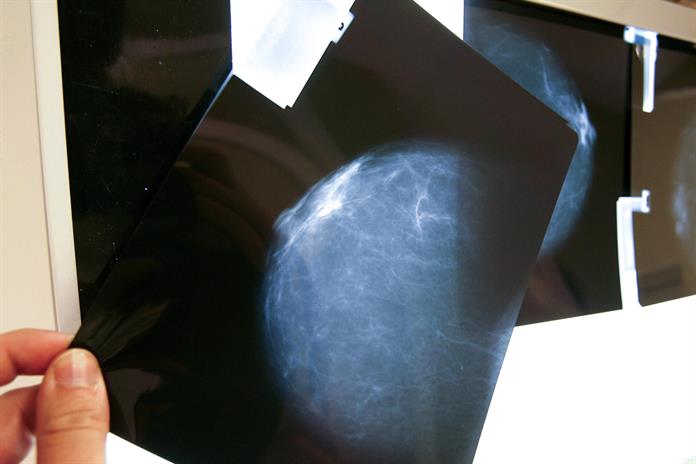

Expertos en el área médica coincidieron en que América Latina enfrenta un reto en la lucha contra el cáncer de mama tras la falta de datos y registros precisos que permitan dimensionar el problema y diseñar políticas efectivas, durante un foro realizado por Diálogos EFE. EFE/ Alex Cruz/ ARCHIVO

“El autoexamen no es para detectar el cáncer, sino para reconocer la normalidad del cuerpo. Las mamografías y ecografías son las que salvan vidas”, enfatizó, tras subrayar la importancia de integrar la educación sanitaria en las escuelas para crear adultos más conscientes de su salud.